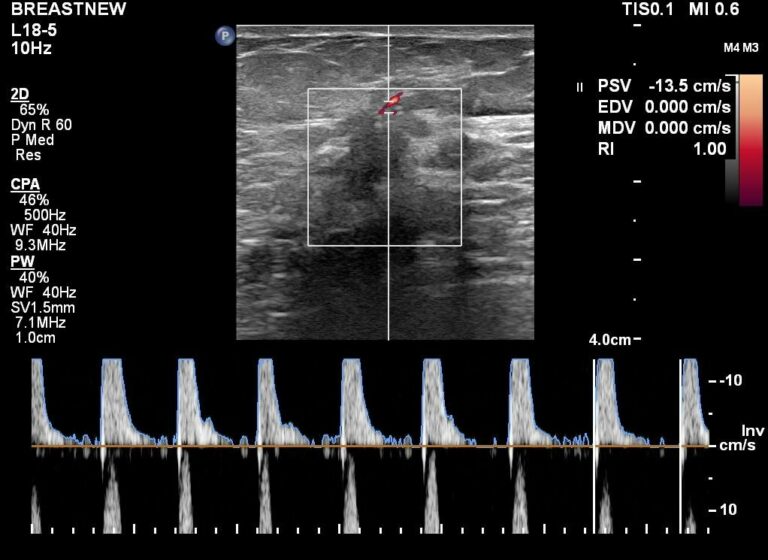

ΥΠΕΡΗΧΟΙ ΚΟΜΟΤΗΝΗ

ΥΠΕΡΗΧΟΣ ΥΨΗΛΗΣ ΕΥΚΡΙΝΕΙΑΣ ΜΕ ΕΛΑΣΤΟΓΡΑΦΙΑ ΚΟΜΟΤΗΝΗ

ΥΠΕΡΗΧΟΙ ΕΠΙΦΑΝΕΙΑΚΩΝ ΟΡΓΑΝΩΝ

ULTRASONİK KOMOTİVİ

ELASTOGRAFİ COMOTİNİ İLE YÜKSEK ÇÖZÜNÜRLÜKLÜ ULTRASON

YÜZEY ORGANLARININ ULTRASONLARI

ULTRASONIC COMOTINI

HIGH DEFINITION ULTRASOUND WITH ELASTOGRAPHY COMOTINI

ULTRASOUNDS OF SURFACE ORGANS